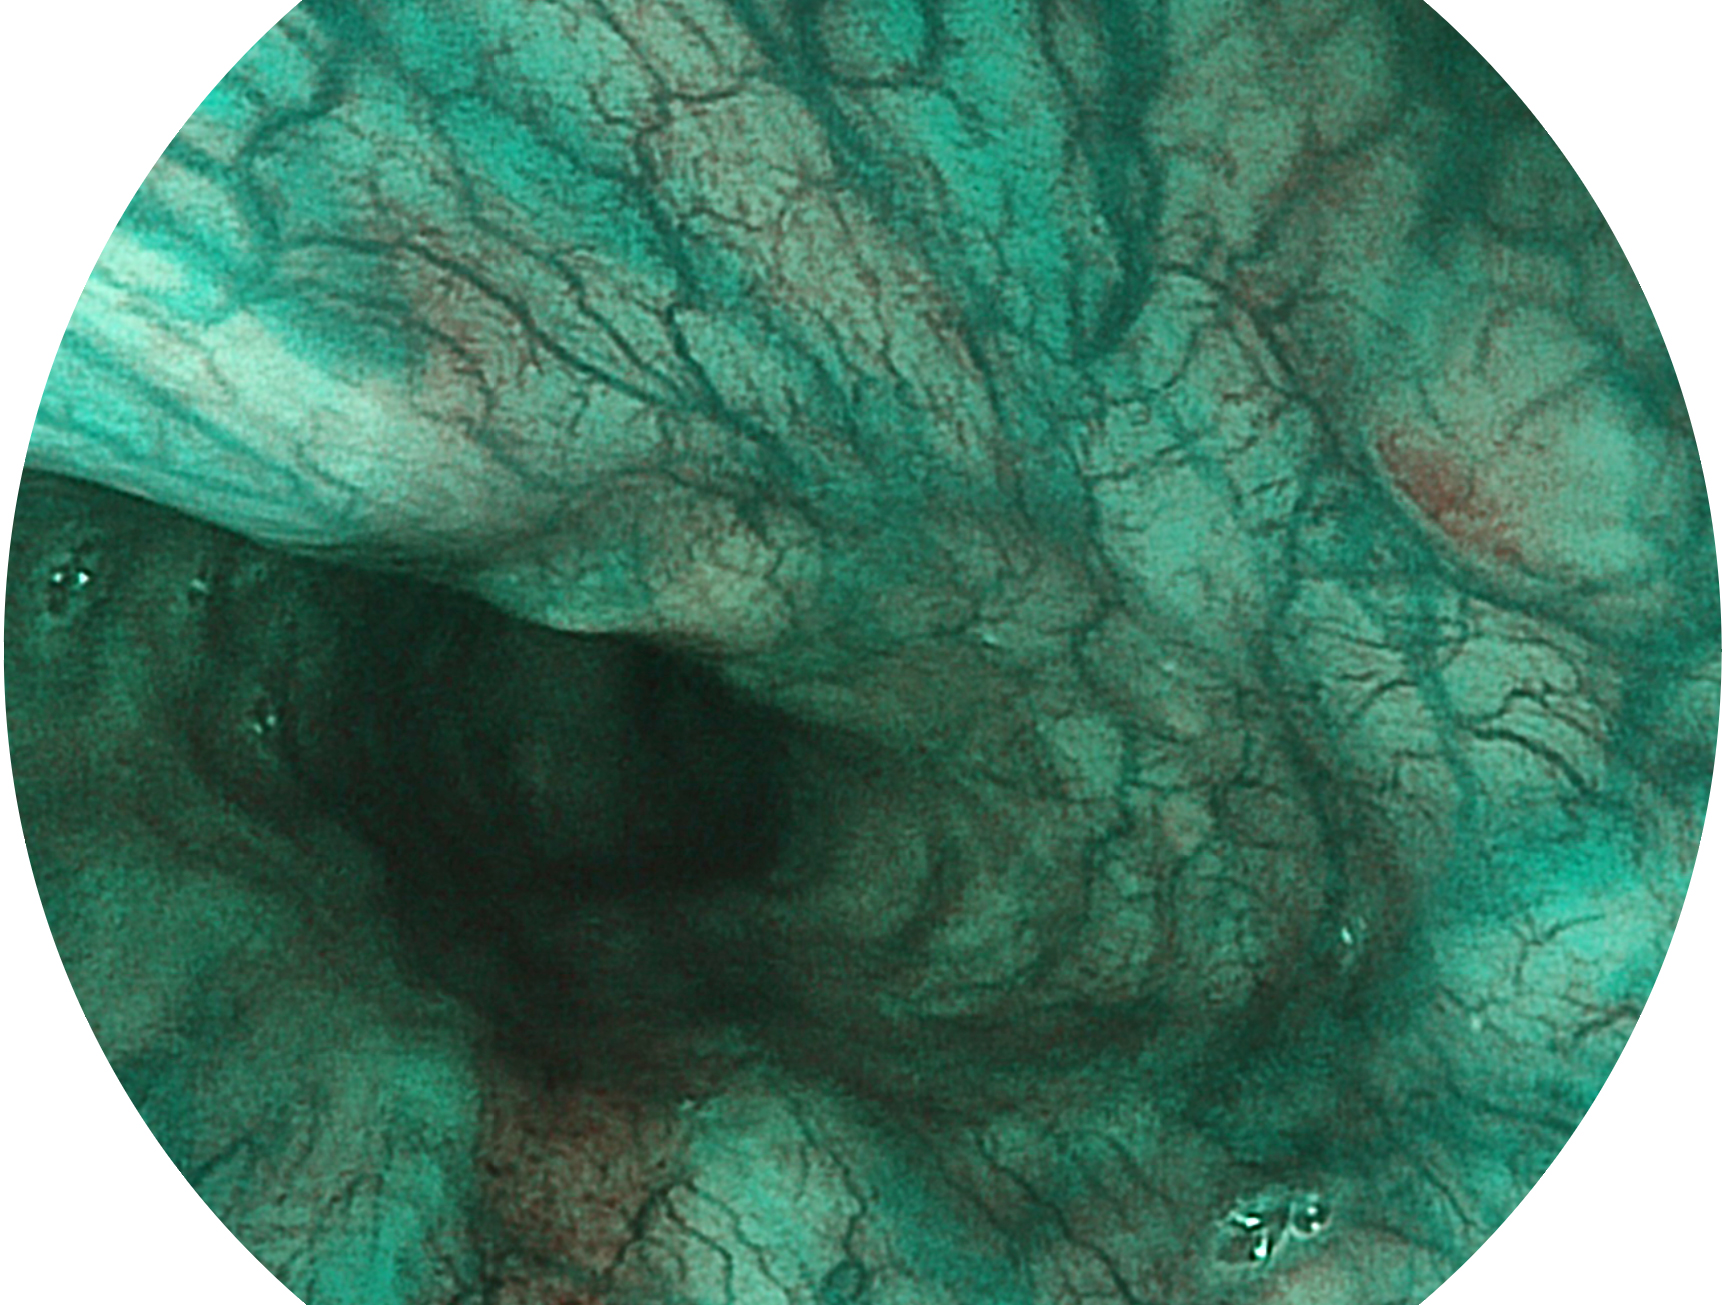

哈哈体育官网新开发的内镜染色技术,主要是基于多波长LED 光源的开发,VLS-55Q 四波长LED 光源是由四个不同颜色的LED光按照相应照明模式所规定的特定发光比例进行合束后形成,合束后形成的照明光的光谱由红光、绿光、蓝光及蓝紫光这四个不同的波段范围构成。具有更高光谱自由度,通过光谱比例的控制,实现了聚谱成像技术,英文全称为“Spectral Focused Imaging, SFI”,缩写为“SFI”和光电复合染色成像技术,英文全称为“Versatile Intelligent Staining Technology, VIST”,缩写为“VIST”。